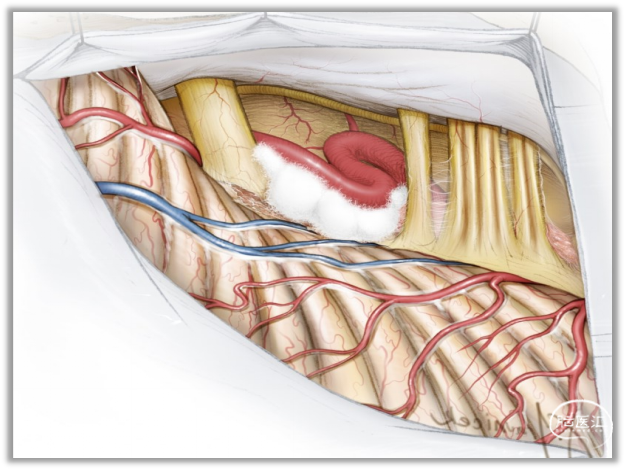

▼15.小脑绒球下入路

小脑绒球下入路(infrafloccular approach)最早由日本专家Matsushima提出。因为绒球和从Luschka孔突出的脉络丛从外侧遮挡面神经REZ区(下图),而且,在绒球和前庭蜗神经之间经常有黏连,还可能存在大量坚韧的蛛网膜小梁,因此从小脑外侧间隙很难暴露REZ区,还可能造成听力损伤。

此时重要的是要牢记面神经出脑干处位于舌咽神经入脑干处上方2~3mm。

绒球下入路(上图)就是抬起小脑的下外侧缘,打开舌咽神经和迷走神经后方的蛛网膜,便可暴露由Luschka孔突出的位于舌咽神经和迷走神经后面的脉络丛,将脉络丛从舌咽神经后缘轻轻分开,以暴露舌咽神经与脑干连接处。脑板进一步向上将脉络丛从舌咽神经后缘上抬起,暴露范围向舌咽神经上方扩展数毫米,此处即为面神经与脑干的连接处(REZ区),恰位于前庭蜗神经的前下方。

▼16.在术中不能直接将小脑牵向中线位,因为与前庭神经平行方向牵拉小脑,拉力会直接传导至神经,增加听力受损的概率。

▼17.锐性地分离后组颅神经的蛛网膜,并辨认出舌咽神经。

充分松解后组颅神经背侧蛛网膜,若松解不充分,就无法获得从下向上的视野。

充分松解的标准就是能看清后组颅神经出入延髓橄榄后沟的神经根丝。

充分释放脑脊液后,此后的操作可不用脑压板,采用吸引器来动态地牵开小脑,动态牵拉既会减少听力受损的概率,也会充分暴露术中所需要的解剖区域。